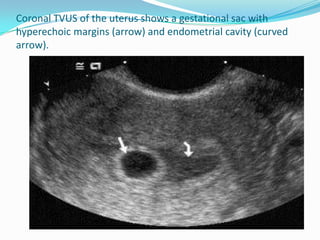

Coronal TVUS of the uterus shows a gestational sac with

hyperechoic margins (arrow) and endometrial cavity (curved

arrow).